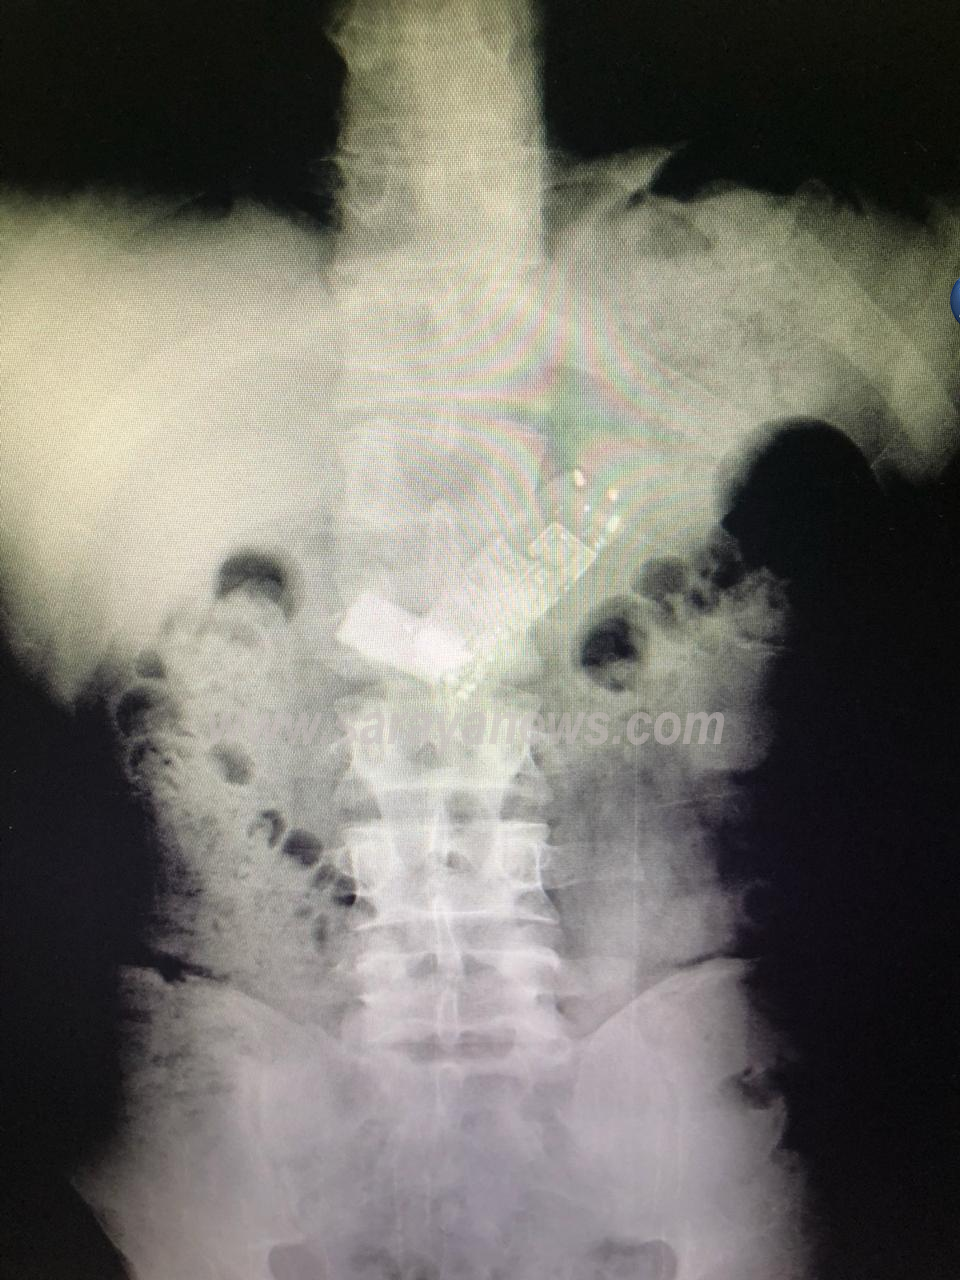

واضاف المصدر لسرايا ؛ انه وبعد تصوير المريض لتشخيص حالته ، تبين وجود هاتف نقال كان قد ابتلعه المريض ، وتم ادخاله الى غرفة العمليات مباشرة.

ولفت المصدر ، انه تم استدعاء رئيس قسم الجراحة الدكتور نايف العبدللات وفريقه الجراحي لمحاولة استخراج الهاتف ، حيث تم اجراء عملية جراحية لاستخراج الهاتف بعد فشل عملية التنظير.